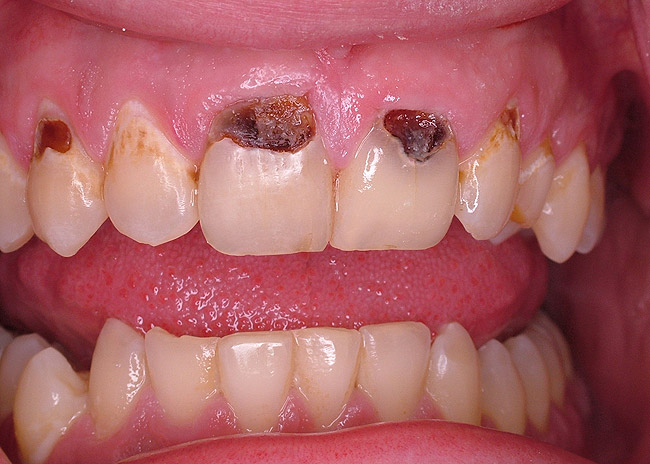

The use of EPT to assess a tooth prior to restorative or endodontic treatment depends on the clinical situation. For teeth with obvious periapical radiolucencies indicative of chronic abscess or cysts, a pulpal vitality test will confirm the diagnosis (Figure 5). In the presence of deep caries, using an EPT can confirm pulp vitality before initiating the restorative procedure (Figure 6 and Figure 7). In the case in which the radiograph demonstrates significant caries near the pulp, the EPT can provide additional information. For this patient with no history of pain in the maxillary first molar, the radiographic and clinical appearance of occlusal caries lead to the use of EPT to demonstrate lack of pulpal vitality (Figure 8). For large Class V carious lesions, the radiograph is usually not helpful in determining potential endodontic needs. Using an EPT provides a more definitive expectation of the extent of the caries relative to the pulp (Figure 9).

Figure 9A Deep Class V caries (pulpal vitality test: no response).

Figure 9A

Figure 9B Removal of caries tooth Nos. 8 and 9 reveals nonvital pulp.

Figure 9B